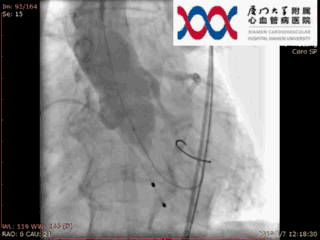

选择23X40mm球囊预扩

根据患者术前 CT分析,这个病人瓣上 40-50mm 处主动脉弥漫性钙化,类似瓷化主动脉弓,钙化中夹有血栓,操作过程中主动脉夹层发生风险高。经术前讨论结合患者左室流出道解剖结构选择低位释放,规避升主动脉夹层风险,同时利用病人特有生理解剖结构规避术后瓣周漏的发生。同时根据四肢血管CT,选择右股动脉为主路径,选择 L29 规格VenusA-Valve 瓣膜。